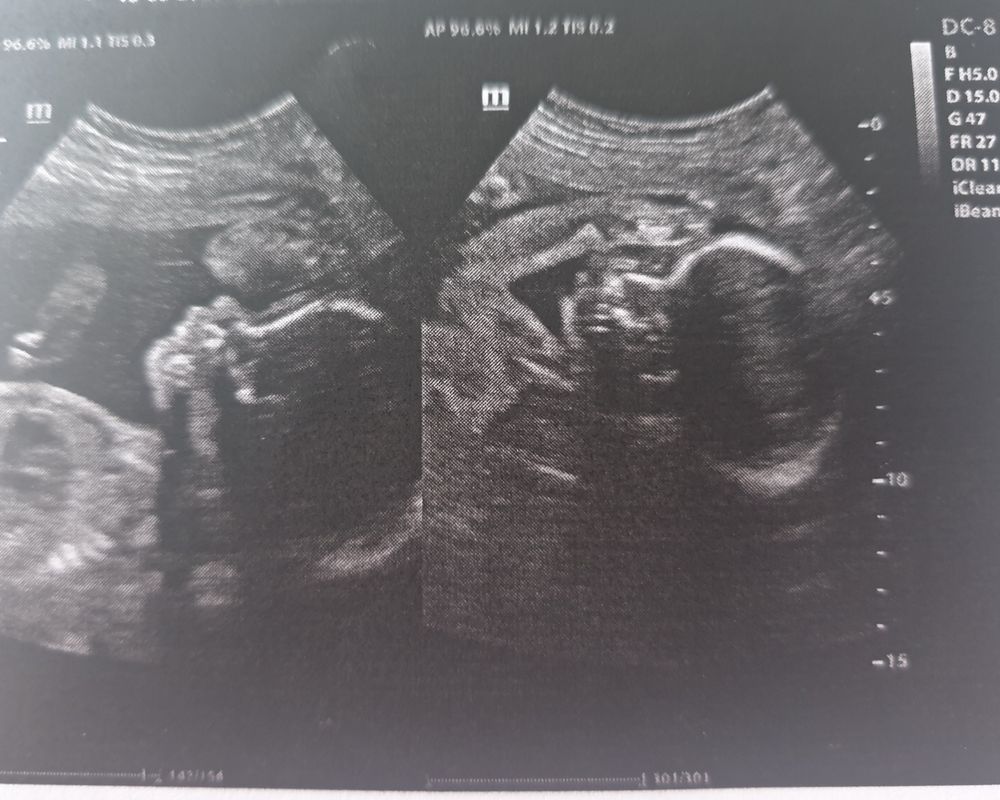

26 недель. Фотопуз. УЗИ с мужем. Отпуск начался 😀

😂 как он мило закрыл личико. Прелесть. Животик у вас хороший, как раз для фс)) А почему сводит икры, не подскажете? А то у меня тоже так было)

С ладошками очень забавно))